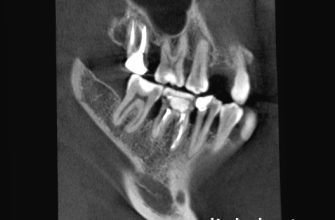

Тип протеза

Различные типы протезов имеют разный срок службы. Например, съемные протезы требуют более тщательного ухода и, как правило, имеют меньший срок службы, чем несъемные. Имплантаты, в свою очередь, при правильном уходе могут прослужить десятки лет. Выбор типа протеза должен осуществляться совместно с врачом-ортопедом, с учетом индивидуальных особенностей пациента и его финансовых возможностей.

| Имплантаты | 20-30 лет и более | Качество имплантатов, гигиена полости рта, состояние костной ткани |